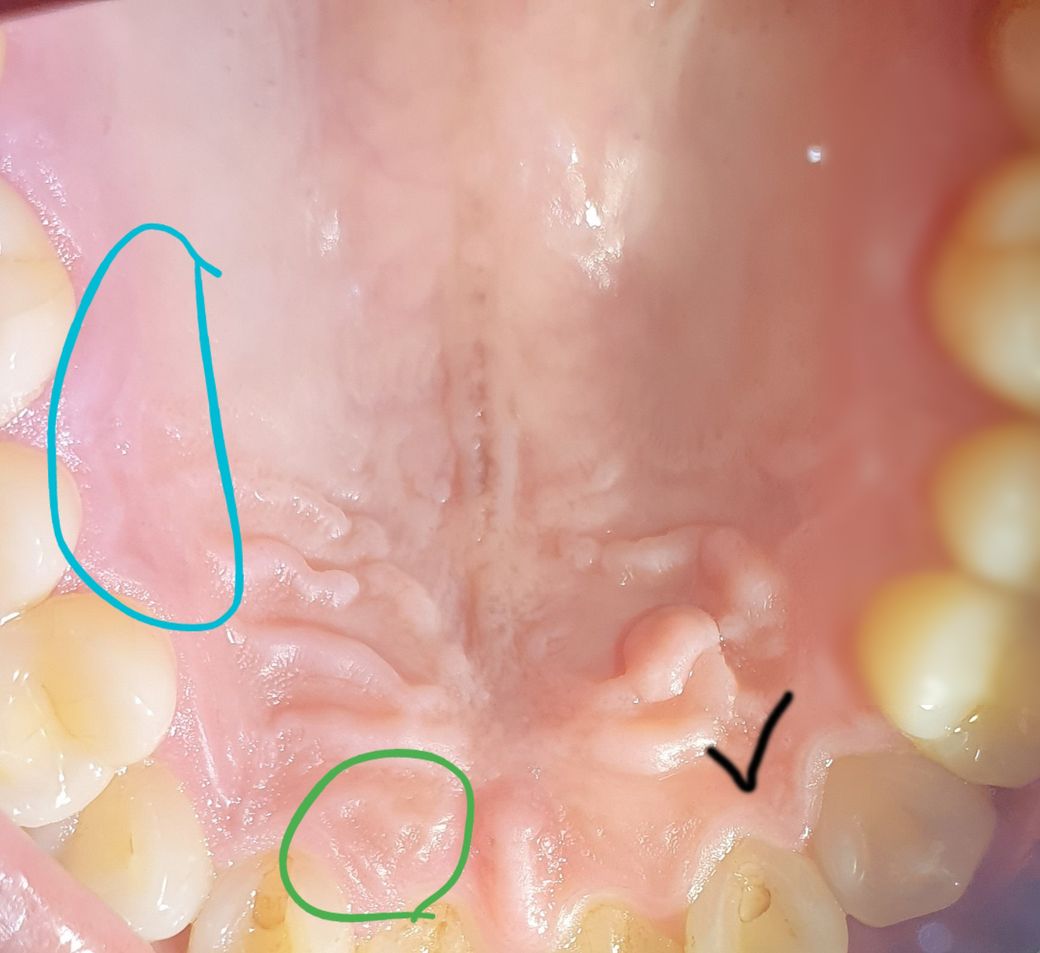

입천장 사진중에

초록동그라미 친부분이 눌린자국이있습니다 괜찮은건가요? 통증이런건없습니다

다만, 검은체크 부분이 기상 후엔 괜찮다가 일상생활하다보면 혀를 갖다대면 얼얼한 느낌이있습니다

앞니 부딪혔을때 얼얼한 통증이라고 해야맞는거같아요

이부분때문에 치과방문하여 저부분만 치근단사진을 찍었었는데 괜찮다고 아무이상이없다고하였습니다

체크부분 통증은 9월 스케일링이후 하루도 빠짐없이 반복중이예요

파란동그라미부분은 혀 갖다대면 간질간질한느낌이들고 가끔 콕콕 따끔? 하는느낌이들었습니다

2일된거같아요 입천장이 저렇게 길게 파인 형태를 띄는지 알수있을까요?

파노라마 사진 상에서는 특별히 큰 문제점은 발견되지 않고 초록 동그라미 친 부분도 palatal rugae 라는 정상구조입니다.